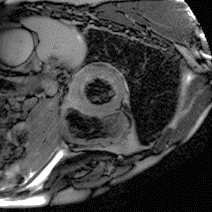

Although supervised deep-learning has achieved promising performance in medical image segmentation, many methods cannot generalize well on unseen data, limiting their real-world applicability. To address this problem, we propose a deep learning-based Bayesian framework, which jointly models image and label statistics, utilizing the domain-irrelevant contour of a medical image for segmentation. Specifically, we first decompose an image into components of contour and basis. Then, we model the expected label as a variable only related to the contour. Finally, we develop a variational Bayesian framework to infer the posterior distributions of these variables, including the contour, the basis, and the label. The framework is implemented with neural networks, thus is referred to as deep Bayesian segmentation. Results on the task of cross-sequence cardiac MRI segmentation show that our method set a new state of the art for model generalizability. Particularly, the BayeSeg model trained with LGE MRI generalized well on T2 images and outperformed other models with great margins, i.e., over 0.47 in terms of average Dice. Our code is available at https://zmiclab.github.io/projects.html.